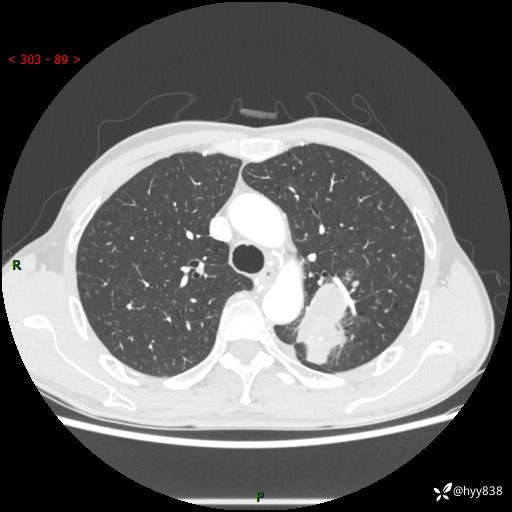

老年男性,咳嗽咳痰伴痰中带血4月。沿支气管铸形生长的不多---结果公布~

现病史:患者余4月前发现咳嗽咳痰伴痰中带血,无胸闷、胸痛、头晕、恶心、呕吐等不适,2天前因体检发现肺部结节遂于当地市第一人民医院行胸部CT薄层平扫+三维重建示:1.左肺上叶尖后段占位性病变考虑肿瘤性病变伴阻塞性肺炎,右肺上叶后段磨玻璃结节。2.肝内多发囊性灶、左肾结石。现患者为求进一步治疗,于我院门诊就诊,门诊以“肺结节”收入院。 自患病以来,精神、饮食、睡眠尚可,大小便正常,体力体重无明显减轻。

胸部CT增强扫描(外院平扫)